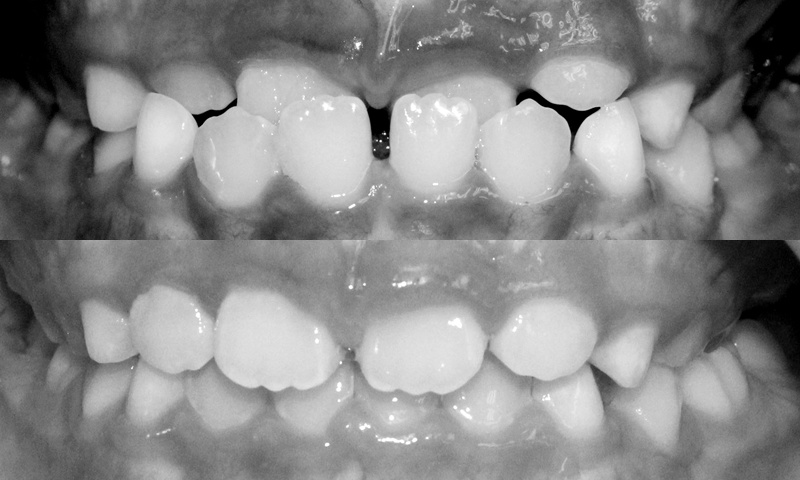

Ví dụ sau đây mà minh chứng:

![]() |

| Bệnh nhân nữ 6 tuổi bị móm, điều trị can thiệp sớm với khí cụ trong 5 tuần. |